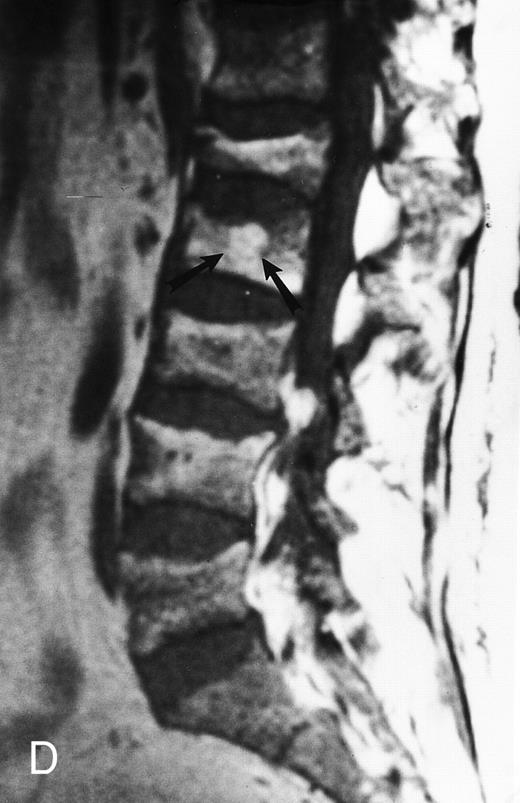

Variegated MR pattern of abnormal marrow in a 45-year-old man with multiple myeloma: T1-weighted (600/20, TR/TE) (A), relatively T2-weighted gradient recalled echo (650/20, TR/TE, flip angle 20°) (B), and enhanced T1-weighted (600/20, TR/TE ) (C) sagittal MR images of the lumbar spine show multiple tiny foci of marrow involvement. Arrows point to island of normal fatty marrow. Sagittal T1-weighted (600/20, TR/TE) MR image 6 months after initiation of chemotherapy (D) shows reappearance of fatty marrow in the spine. Note development of multiple vertebral collapses. T1-weighted MR image 1 year after bone marrow transplantation and total body irradiation (600/20, TR/TE) (E) shows resolution of marrow abnormality and homogeneous bright signal of fatty marrow in the lumbar spine. Note progression of compression fractures. Reprinted with permission from Moulopoulos et al.14,21